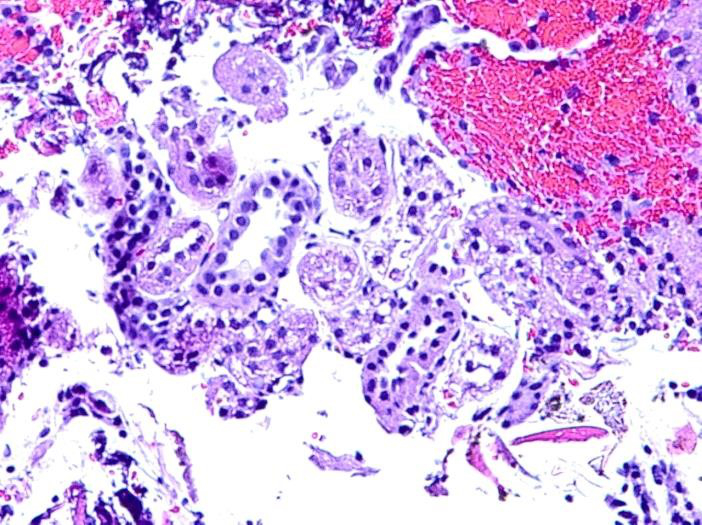

Background: Endoscopic ultrasound guided fine-needle aspiration (EUS-FNA) is the most widely used method for obtaining diagnostic material from lesions immediately adjacent to the gastrointestinal tract. Fine needle aspiration is performed by obtaining a diagnostic tissue sample from suspected tumor lesions. Using the woodpecker technique, the endoscopist plunges the needle into a target tissue 10-15 times in order to mince a lesion for aspiration of cellular material. As a result, the aspirate is often devoid of the cells required for pathologic evaluation, and preservation tissue morphology is not possible. Shown below is a cytology smear obtained through EUS FNA with the current state of the art instruments.

Cells obtained through EUS FNA from an islet cell tumor of the pancreas